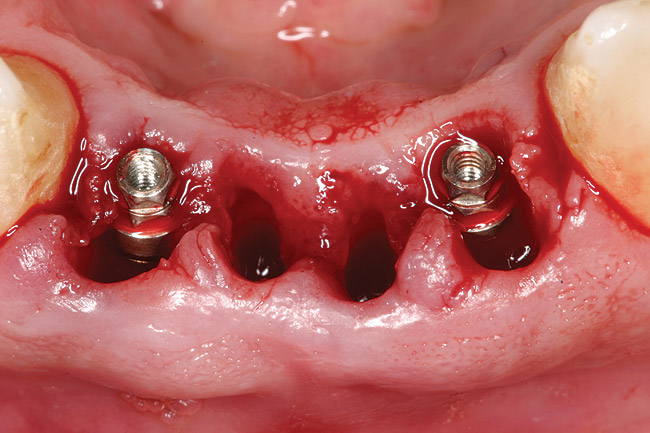

Figure 4  Implants were placed without flap elevation.

Figure 4

Preoperatively, 1 g of amoxicillin was administered. Using local anesthesia (lidocaine 1:100,000 epinephrine), extractions of teeth Nos. 23 to 26 were performed without raising a flap and with gentle luxation to preserve the remaining facial osseous plate. The sockets were curetted prior to implant placement. A vacuum-formed surgical guide, fabricated based on a diagnostic wax-up of the desired tooth positions for the subsequent fixed prosthesis, was used during implant placement. Osteotomies were performed at site Nos. 23 and 26 and positioned toward the lingual aspects of the sockets (Figure 3 and Figure 4). Two tapered implants (OsseoTite™ 313, BIOMET 3i™, www.biomet3i.com) measuring 3.25 mm x 13 mm were placed. Conical prosthetic abutments (3-mm height) were used to facilitate joining the two implants in a screw-retained FPD (Figure 5). A laboratory-processed acrylic-resin provisional restoration was altered to allow connection to the temporary cylinders. The provisional was placed into the vacuum-formed surgical guide that was now used to maintain the provisional in the correct 3-dimensional position (Figure 6) while being attached to the temporary cylinders with acrylic resin intraorally. Once a sufficient amount of acrylic resin was placed to secure the cylinders to the provisional, it was removed from the mouth and its contours were completed at the laboratory bench (Figure 7). The two central incisor sockets were grafted with small-particle allograft material (Puros® Allograft, Zimmer Dental, www.zimmer.com) to maintain the gingival architecture beneath the two ovate pontics (Figure 8). The provisional restoration was inserted and the screws were tightened to 20 Ncm of torque.